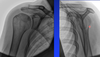

Vad omsluter trochlea i armbågsleden och hur många grader görs detta?

olecranon omsluter trochlea 180 grader

Vilken typ av led är armbågsleden?